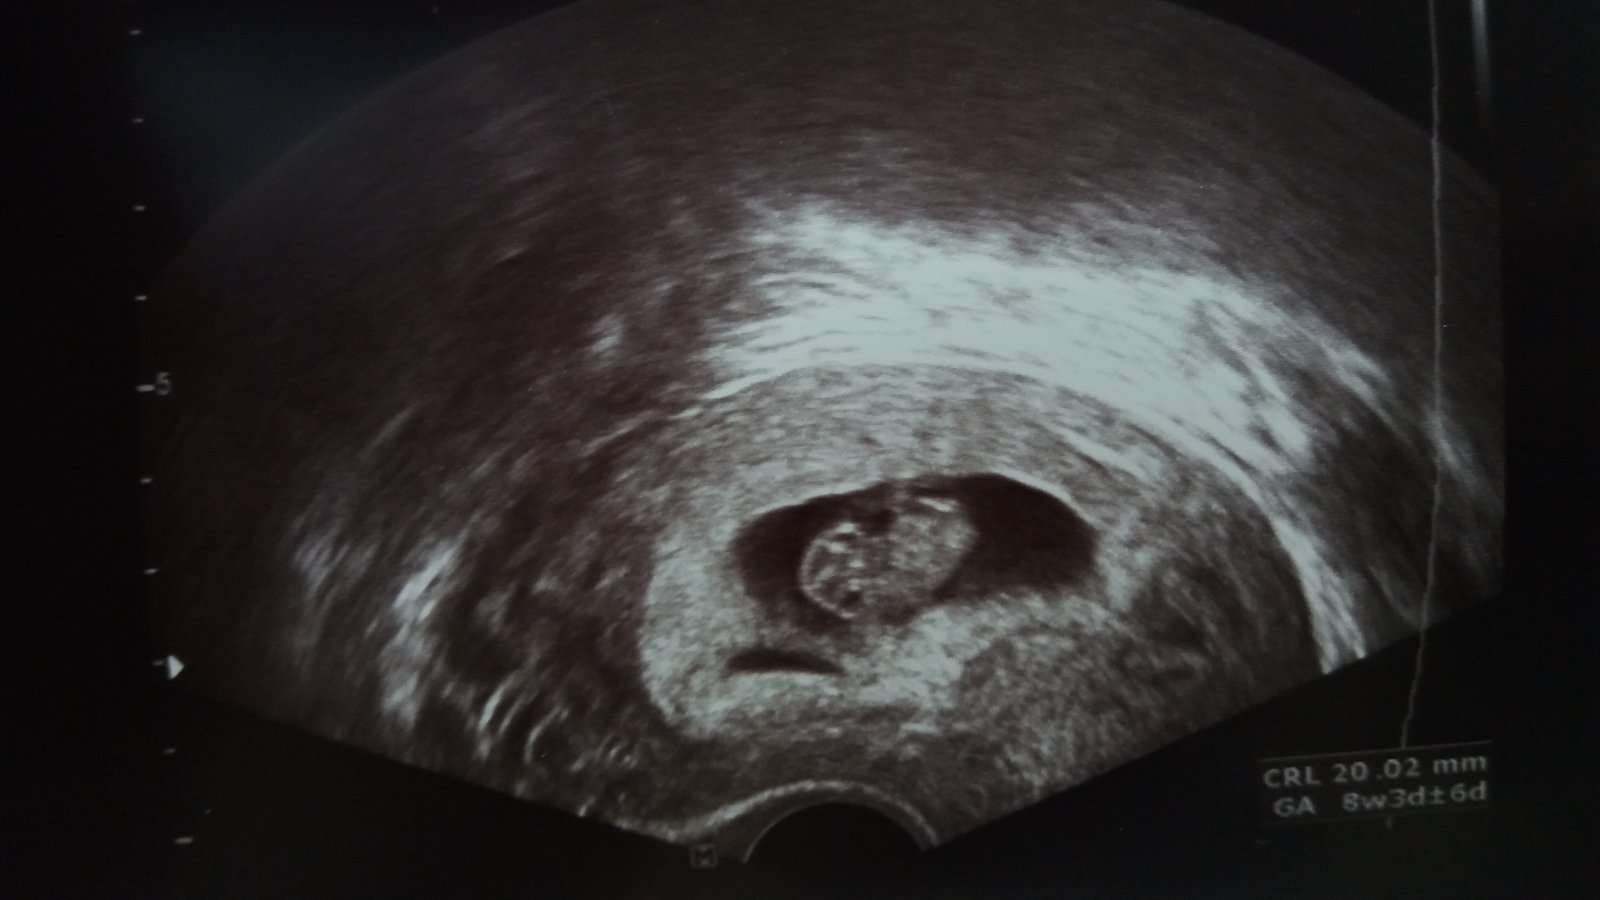

Máme po kontrole, miminko hezky roste, má 2cm ❤ Dnes jsem slyšela i srdíčko a 4.3 jdu na odběry 🙂 Ten den se objednám i na screening a já věřím, že miminko bude v pořádku. Průkazku zatím nemám, tak snad na příští kontrole 🙂

@monib66 povedená fotečka ❤️ Mám radost, že je vše v pořádku 🙏🏻🍀

@monib66 to je krásný snimecek, já tam mám vidět jen takovou malou zizalku 😀 ale jinak super že je vše v pořádku, určitě to tak půjde i dál 😉 kdy jdeš na další kontrolu? Já až za mesic